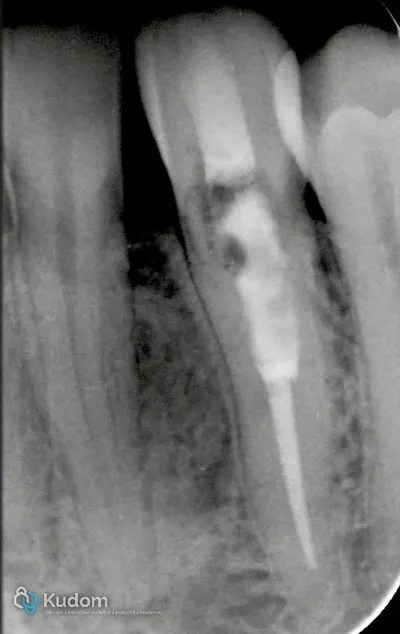

Trattamento endodontico di un primo molare mascellare, con attenzione alla corretta detersione, sagomatura e otturazione.